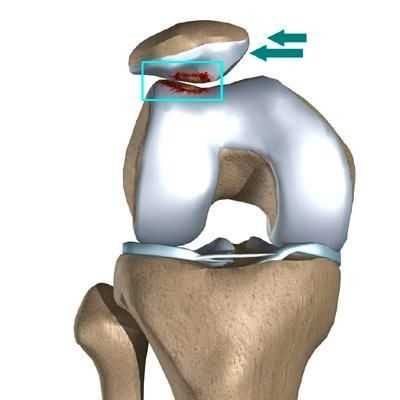

Из-за постоянных микротравм обрывается много капилляров, но кровоснабжение в большеберцовой кости не нарушается. Это приводит к кровоизлиянию, и у пациентов появляются синяки диаметром 1–3 см. Если не прекратить тренировки, начинается отрыв надкостницы вместе с костным фрагментом (апофизом). На месте отрыва формируется костная мозоль и бугристость становится заметной [10] [12] .

При болезни Осгуда — Шляттера выделяют 3 типа отрывного перелома:

- Тип I — фрагмент смещён незначительно. Пациента беспокоит умеренная боль (3–4 балла по 10-бальной шкале боли) во время спортивных занятий. Операция не требуется, достаточно консервативного лечения: не сгибать колено и принимать обезболивающие препараты (НПВС) при болях, уменьшить физические нагрузки, скорректировать питание и увеличить потребление витамина D.

- Тип II — небольшой отрыв в области бугристости большеберцовой кости. Пациент жалуется на умеренную боль (5–6 баллов) во время спортивных занятий и подвижных игр, боль сохраняется и после нагрузки. Если НПВС не приносят облегчения, может потребоваться операция.

- Тип III — отрыв апофиза большеберцовой кости. В этом случае консервативное лечение не помогает, поэтому требуется операция [16] . Пациента беспокоит умеренная боль (5–6 баллов) при небольшой нагрузке, например 15-минутной прогулке или подвижных играх. Пациент может опираться на ногу, но боль не проходит даже после приёма обезболивающих. Травмы или обширной гематомы в месте прикрепления связки надколенника нет.

Фрагментацию с отрывом костного фрагмента лучше всего видно на боковой рентгенограмме [10] .

![Отрыв фрагмента кости [17]](/pimg3/privichniy-vivix-nadkolennika-4DB2D05.jpeg)